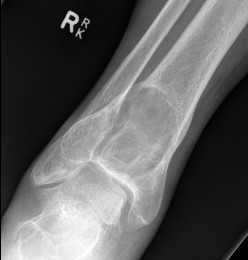

X-ray

Eccentric, sharply demarcated lytic lesion

- no sclerosis around lesion

- narrow zone of transition

- metaphysis, extending into epiphysis

- no mineralization